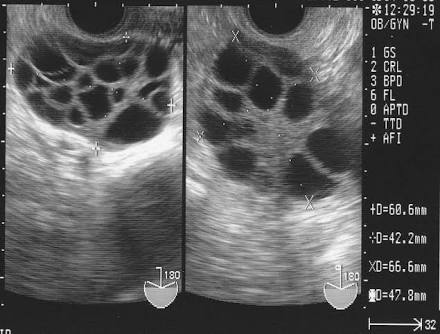

お腹の中には既に六つ子の胎児が確認でき、男の子3人、女の子3人に別れている。

医師は「超音波画像を見たが、六つ子は非常に珍しい。現在全ての胎児は健康状態で、3人の男の子と女の子が確認できる」としている。+332

【簡単に説明すると】 ・3人の子どもがいる夫婦の妻が妊娠 ・超音波検査の結果、6つ子だった ・男の子と女の子3人ずつ。